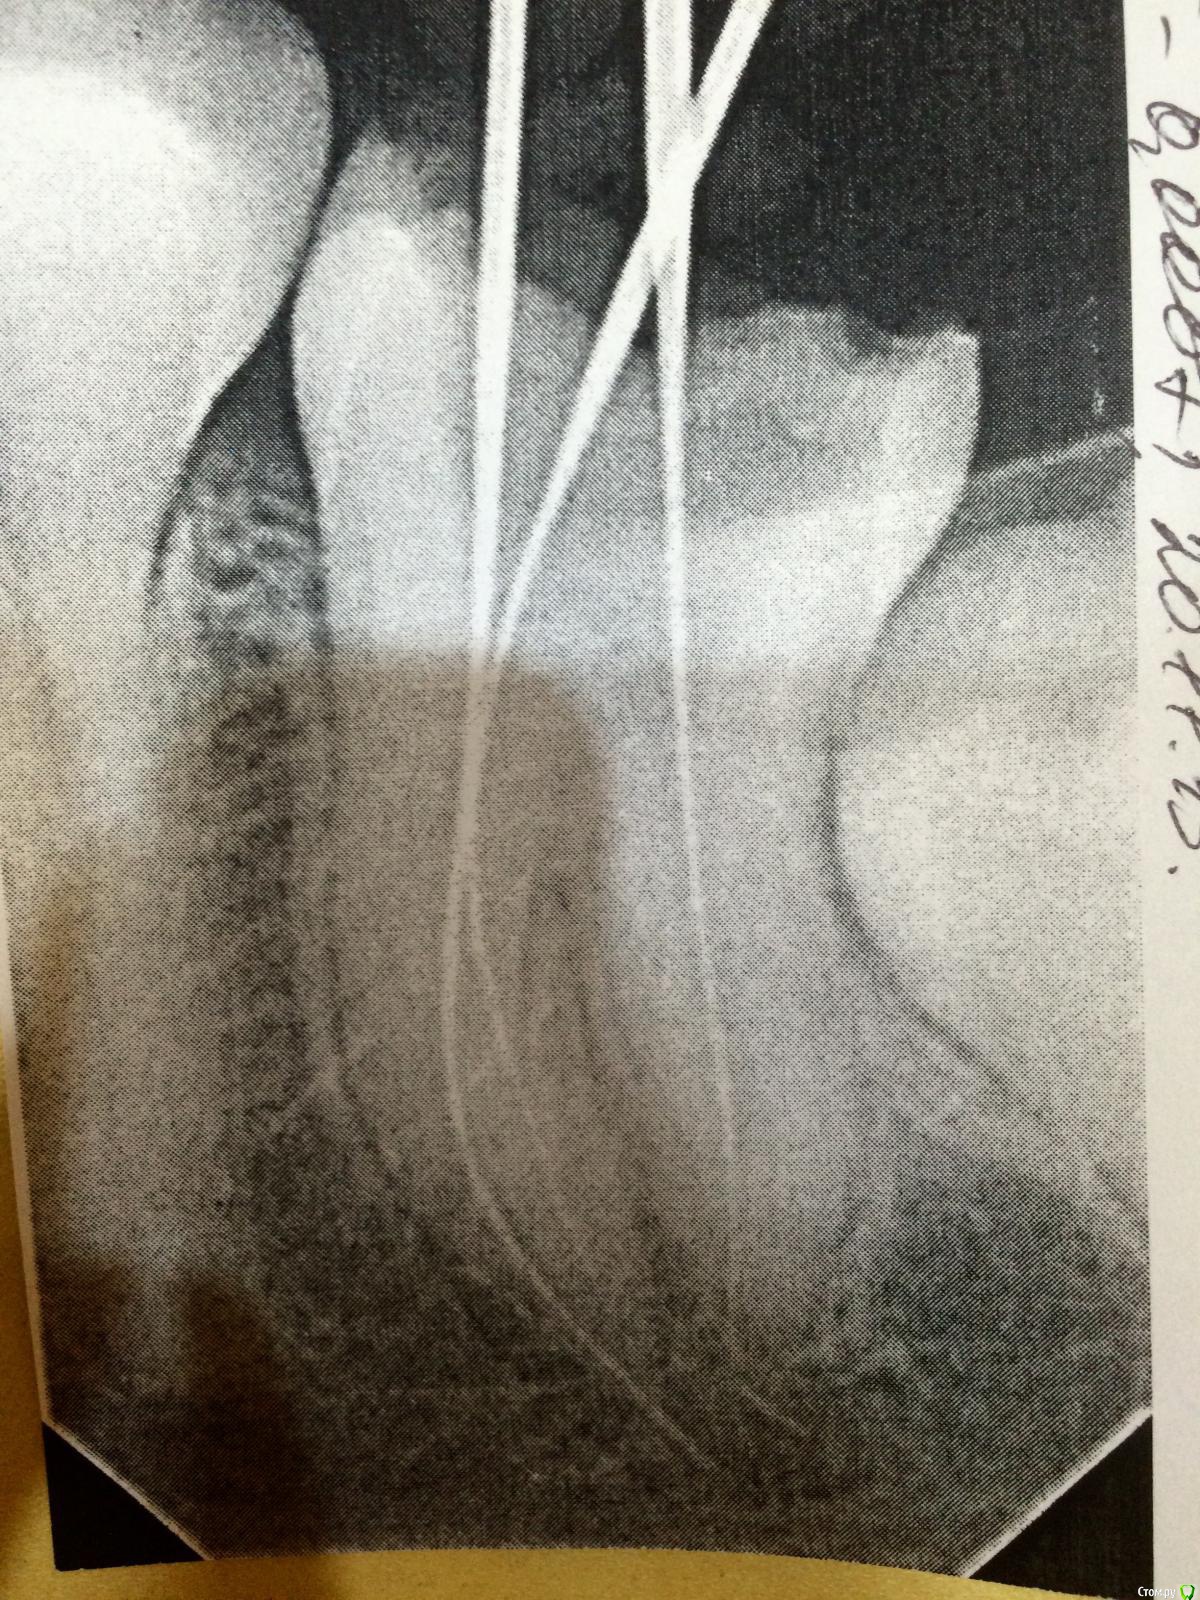

Belladonna.feo Опубликовано 20 ноября, 2015 Поделиться Опубликовано 20 ноября, 2015 (изменено) Диагноз хр. Пульпит. Первичная эндо. Узкие каналы. М/щ не пускает до апекса никаким инструментом. Только 10 файл на длину на снимке. 15 входит лишь на половину пройденной длины. Мою парканом и водой. + рс преп. Как расширить, что ещё сделать? Изменено 20 ноября, 2015 пользователем Belladonna.feo Ссылка на комментарий

vse32 Опубликовано 4 декабря, 2015 Поделиться Опубликовано 4 декабря, 2015 Диагноз хр. Пульпит. Первичная эндо. Узкие каналы. М/щ не пускает до апекса никаким инструментом. Только 10 файл на длину на снимке. 15 входит лишь на половину пройденной длины. Мою парканом и водой. + рс преп. Как расширить, что ещё сделать?image.jpeg А мне кажется, или в дистальном уже есть отломок за апексом? 2 Ссылка на комментарий